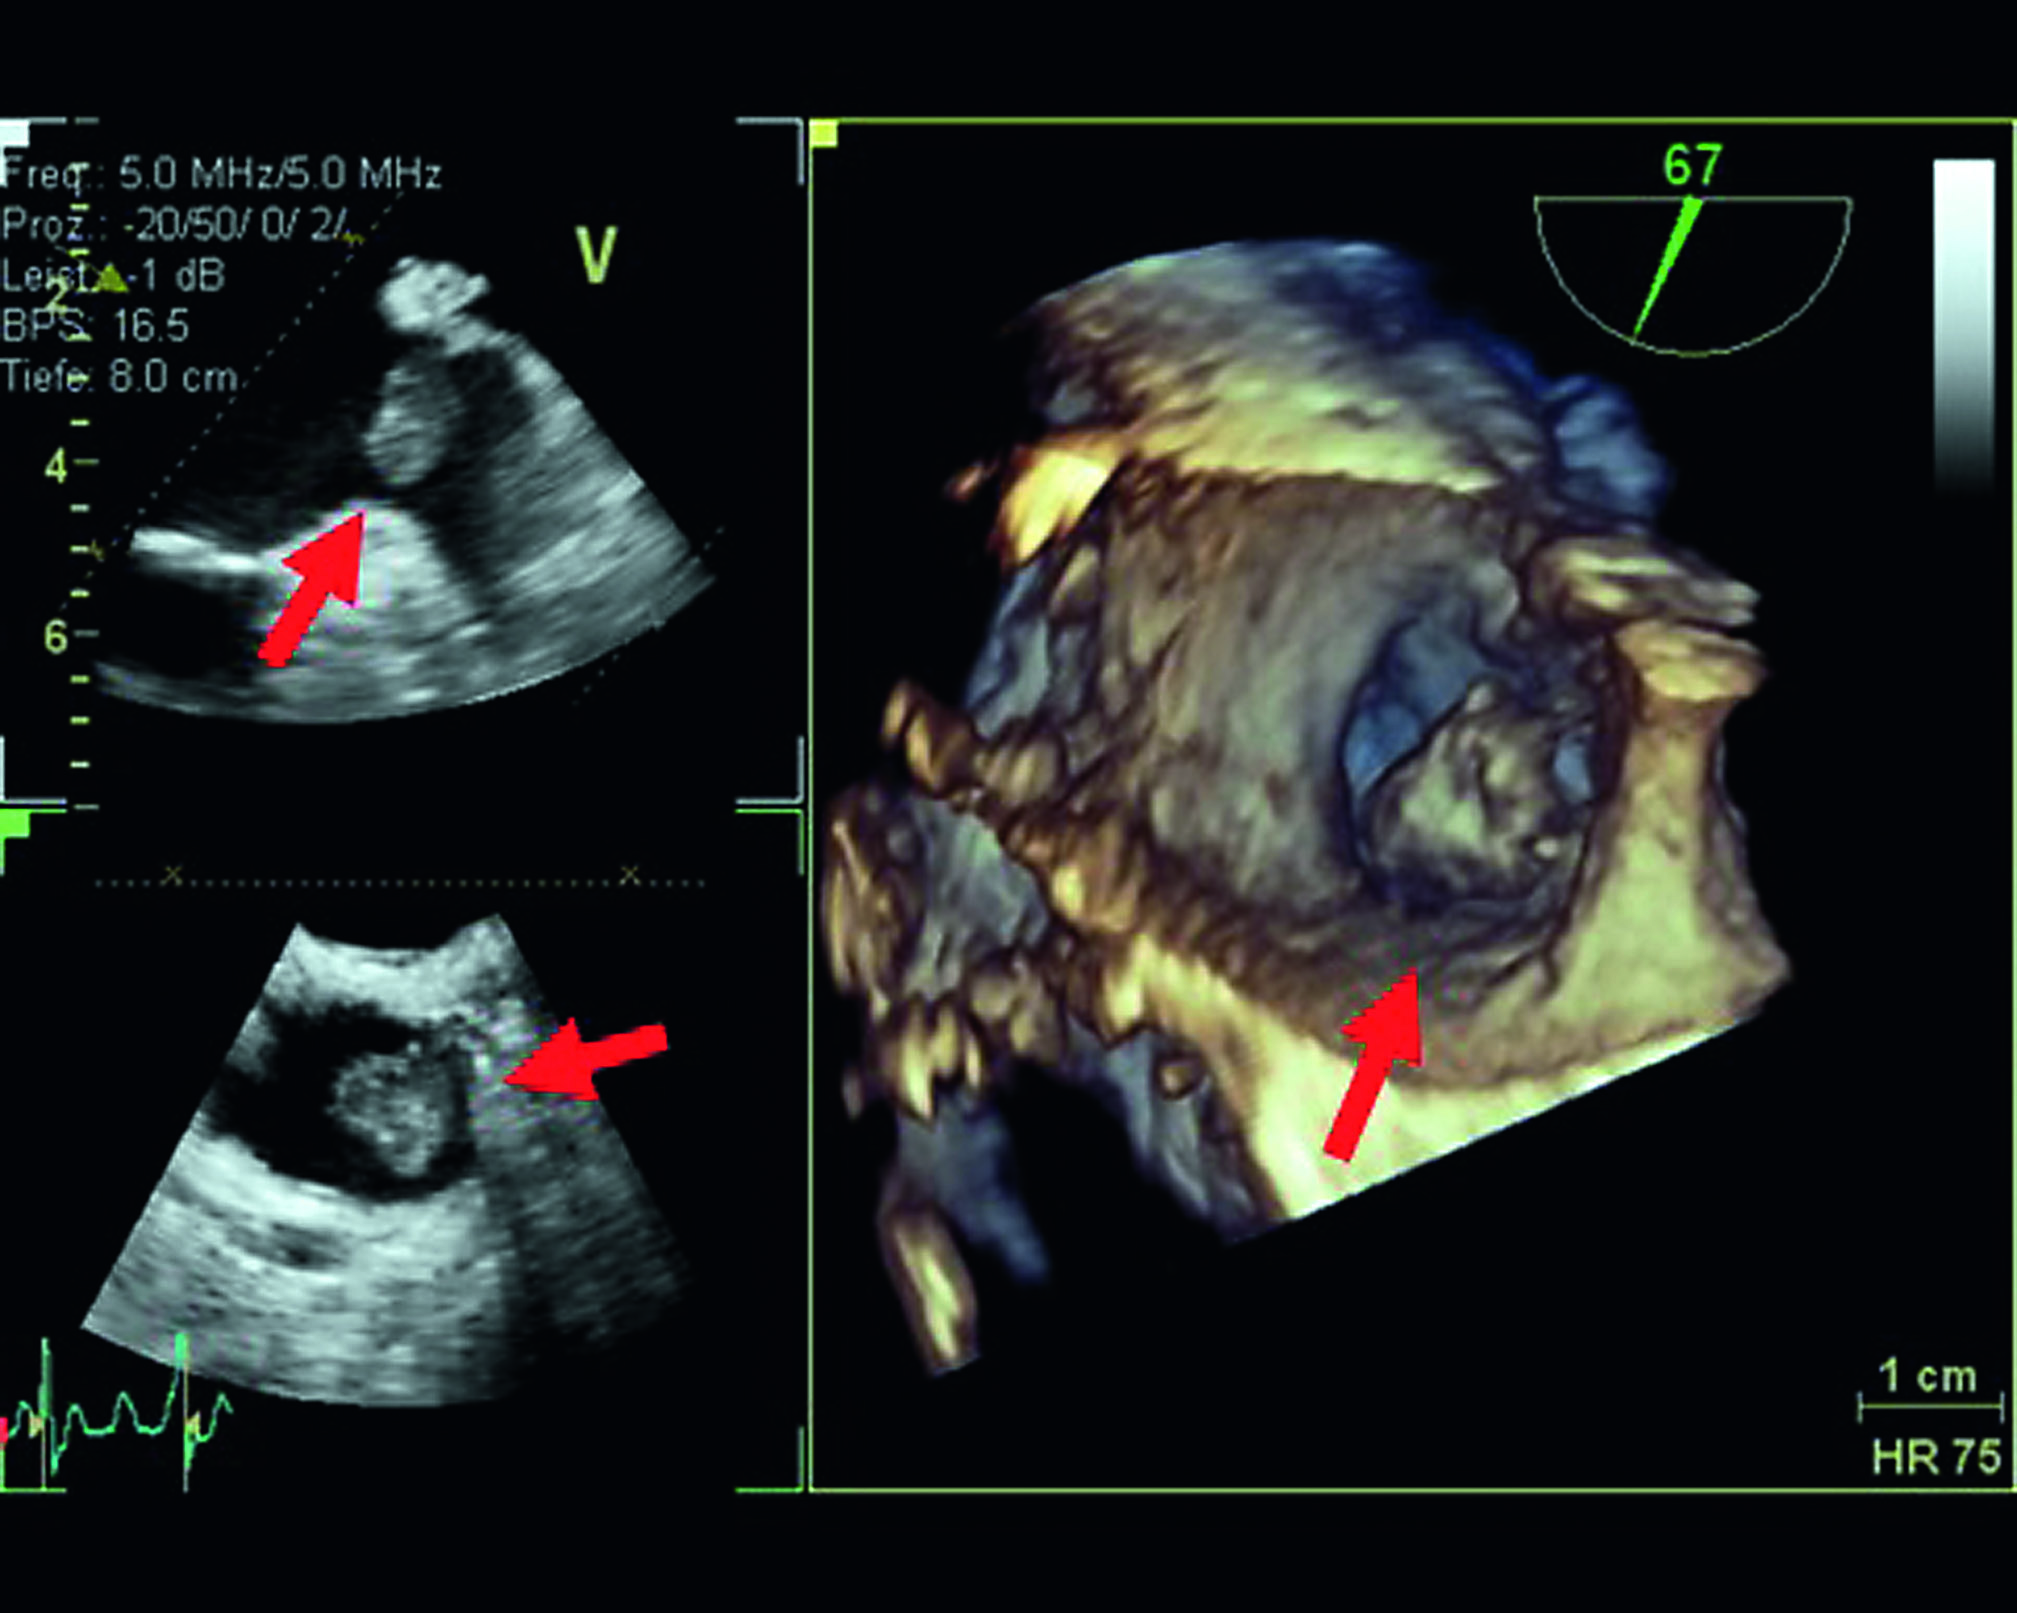

Unbehandelt und ohne schützende Wirkung gerinnungshemmender Medikamente („Blutverdünner“) sind Betroffene mit Vorhofflimmern schutzlos dem Schlaganfall ausgesetzt. Aufgrund des unregelmäßigen Herzschlags bei Vorhofflimmern können sich im Herzen, in einer Ausbuchtung des Vorhofs (sog. Herzohr), Blutgerinnsel bilden. Werden diese ausgeschwemmt und gelangen mit dem Blutstrom in den Kopf, verstopfen sie ein Hirngefäß: Schlaganfall! Jedes Jahr verursacht Vorhofflimmern über 35.000 Schlaganfälle in Deutschland. Da die Ursachen für Vorhofflimmern und Schlaganfall ähnlich sind, ist neben der Einnahme gerinnungshemmender Medikamente (Infos: www.herzstiftung.de) zudem wichtig, auch die Grunderkrankung von Vorhofflimmern konsequent zu behandeln.